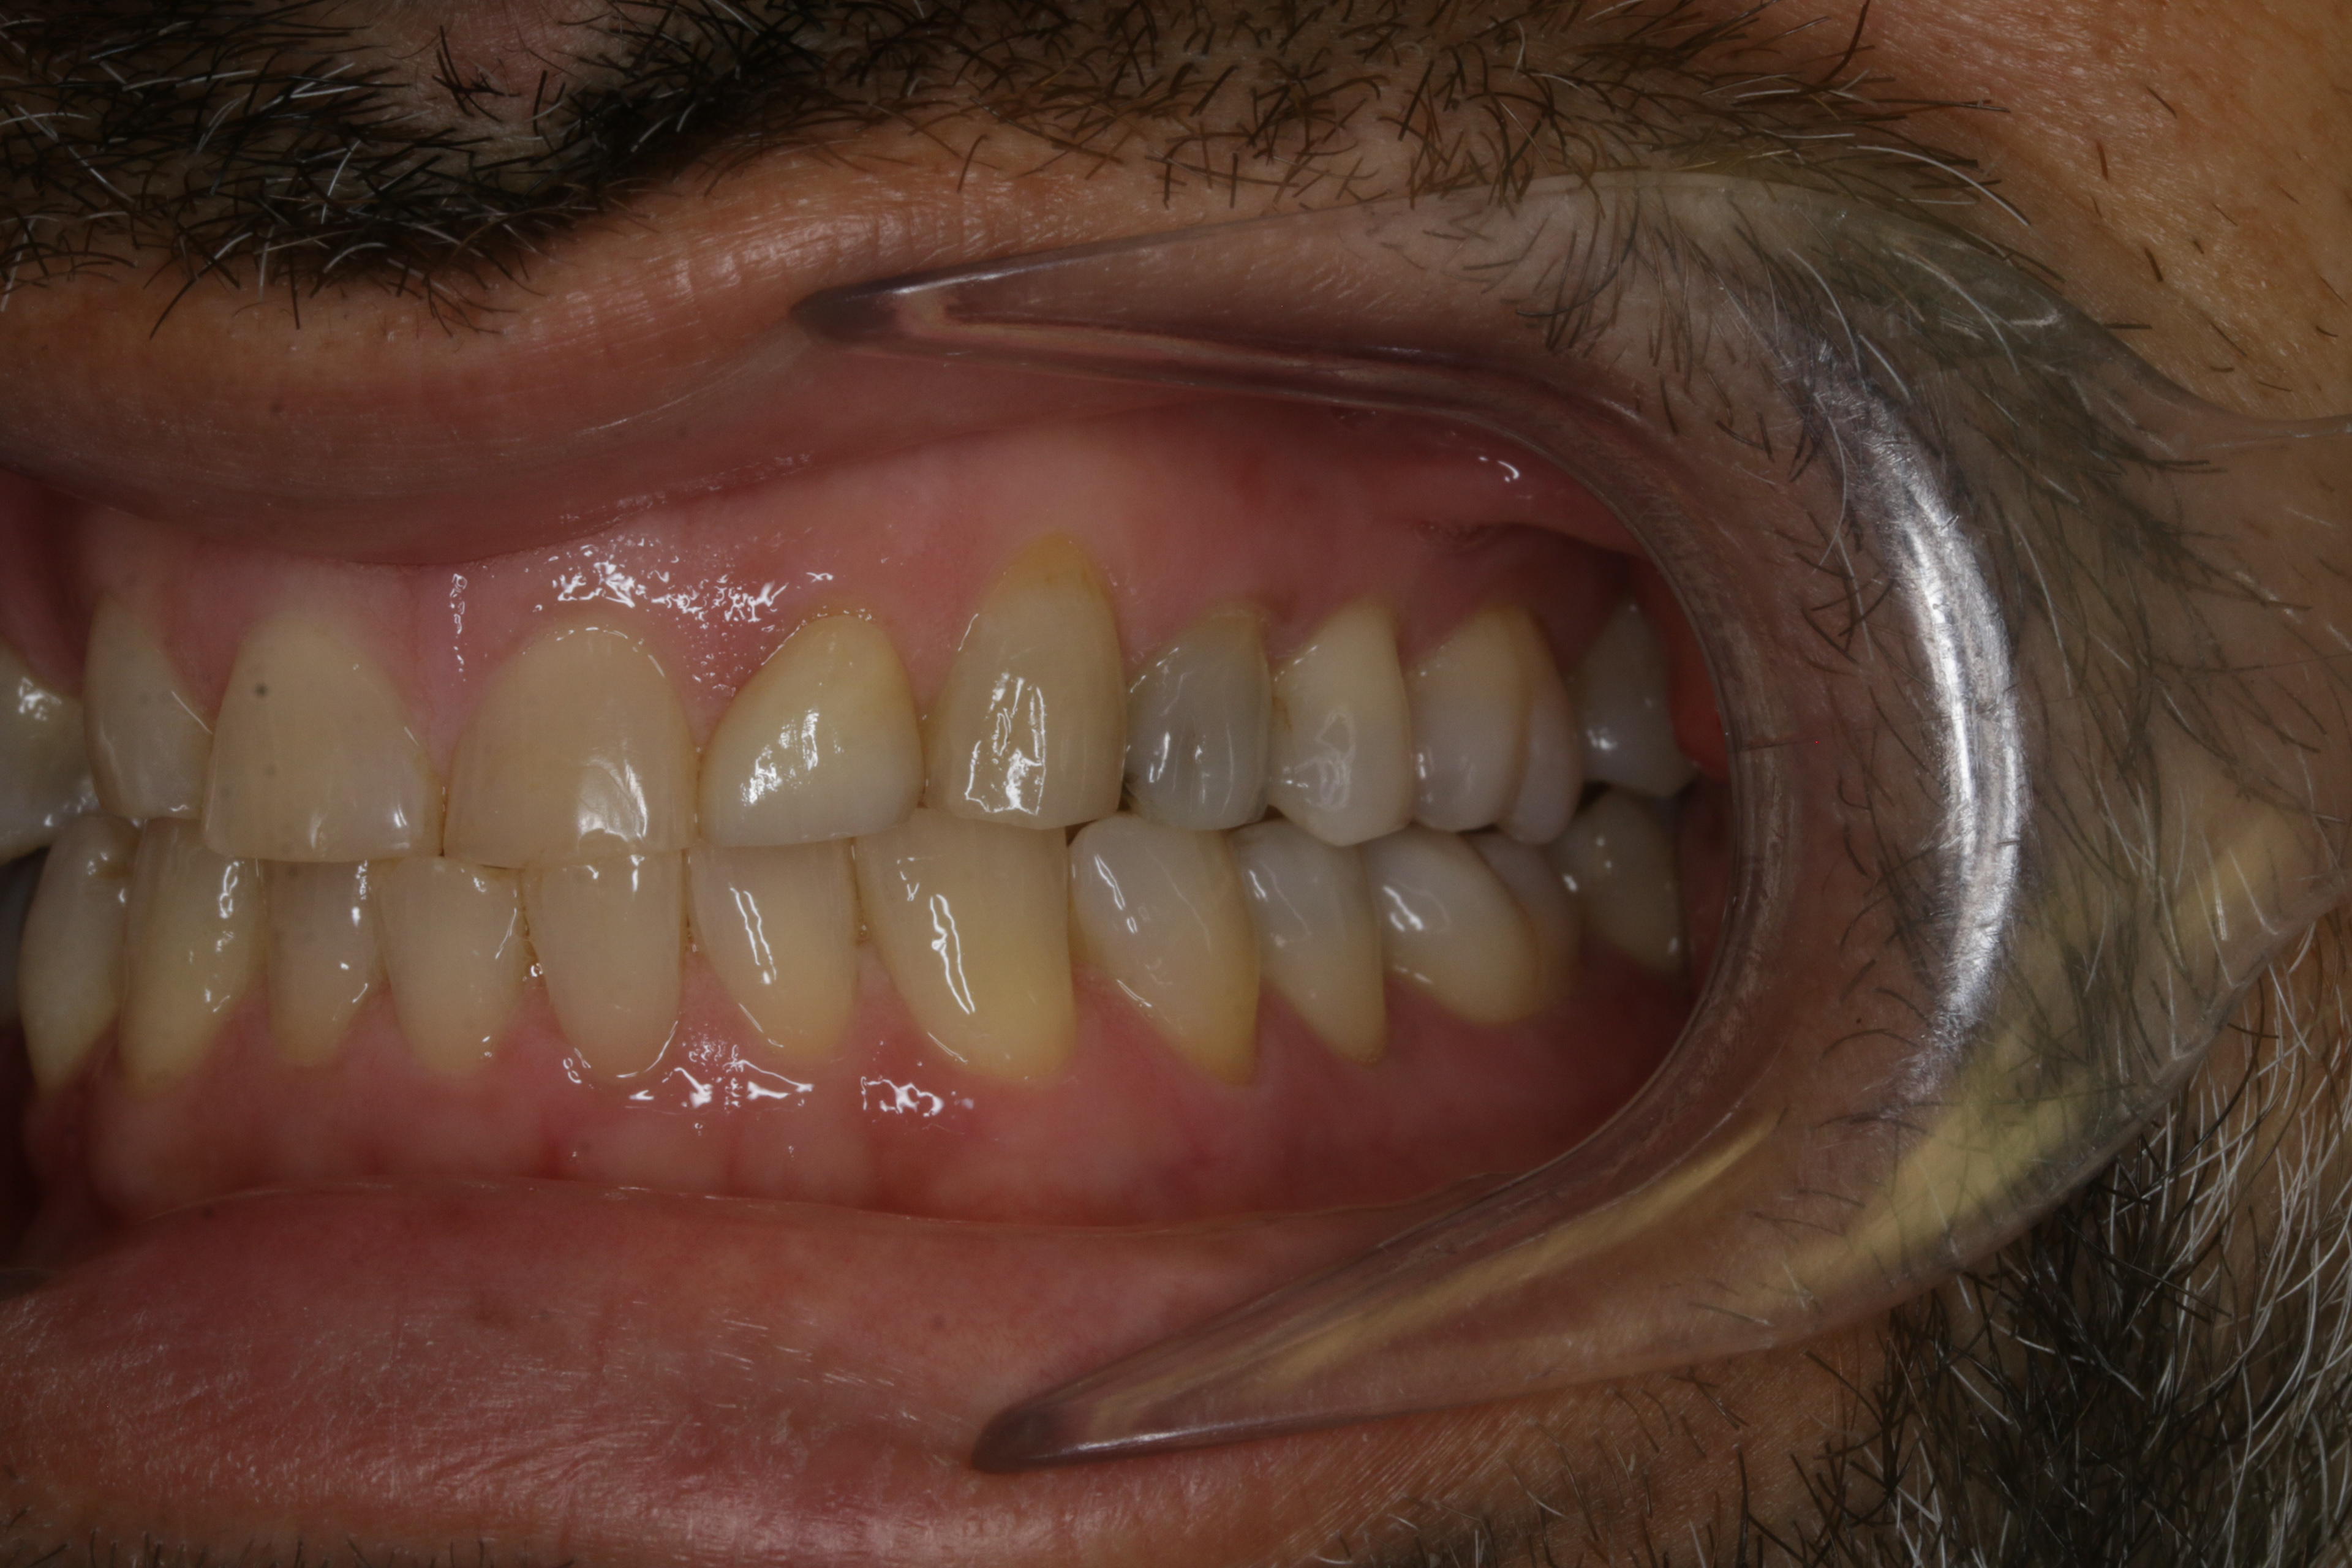

INITIAL RECORDS

BEFORE

BEFORE LEFT SIDE

BEFORE RIGHT SIDE